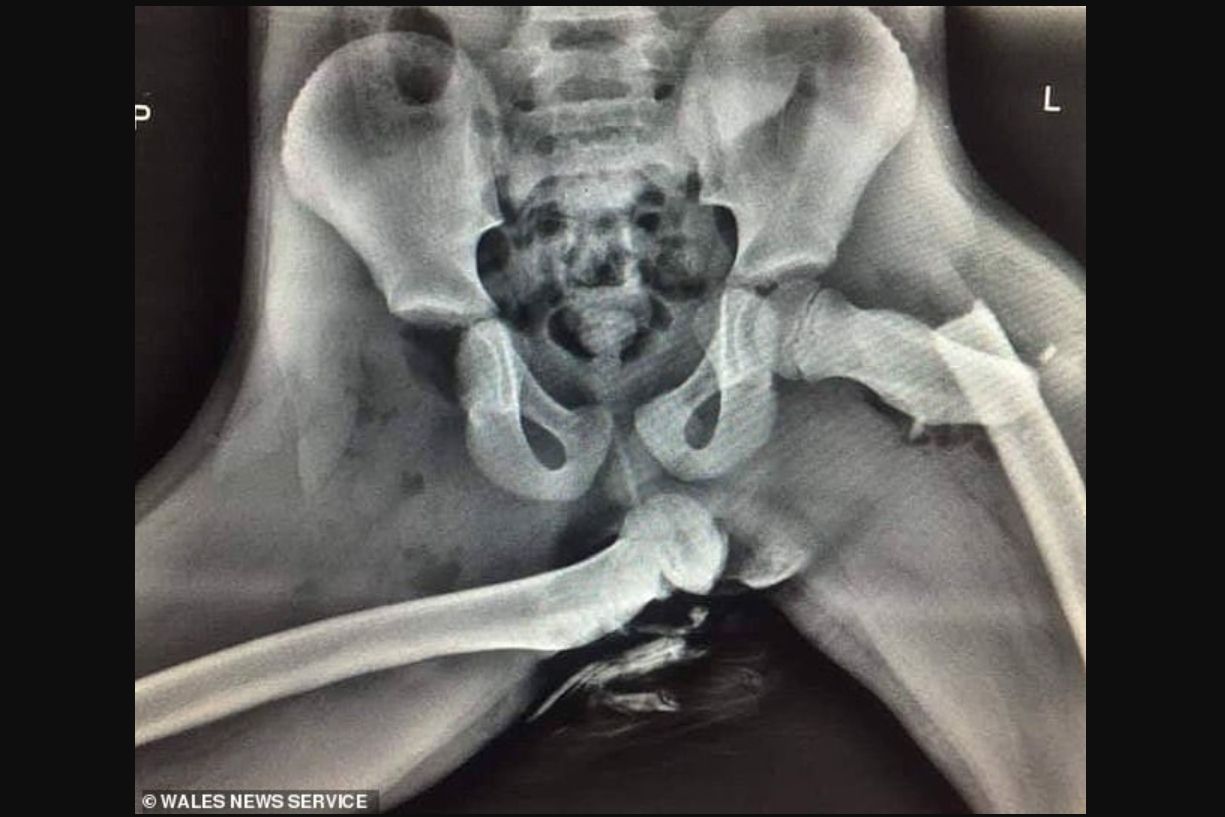

Anggota Kepolisian Dyfed-Powys di Wales, Sersan Ian Price, seperti dikutip situs Dailymail UK, mengunggah foto X-Ray mengerikan. Unggahan ini ditujukan sebagai peringatan agar tidak meletakkan kaki di dasbor. Ia menjelaskan,"Foto X-Ray ini merupakan cedera memilukan. Terjadi pada penumpang depan yang kakinya menyandar di dasbor saat kecelakaan terjadi." Ia menambahkan, "Jika penumpang Anda melakukan hal serupa, hentikan kendaraan dan berikan foto ini."

Jelas tercermin dari hasil sinar-X dampak fatal sebuah tindakan ceroboh. Tulang paha kiri patah, dan satu lagi dislokasi. Tak hanya itu, fraktur juga terjadi pada tulang hidung, pergelangan, dan bahu. Ini merupakan kejadian nahas yang dialami Audra Tatum di Chickamauga, Georgia, AS. Nyawa tidak melayang namun cedera dideskripsikan ‘mengubah hidup’.

Penyebab parahnya cedera adalah airbag dan tidak mengenakan sabuk pengaman. Kantong udara yang mengembang sangat cepat dan kuat memang didesain untuk meredam momentum tubuh kala terhentak. Berperan sebagai bantalan agar kepala atau badan tidak langsung menghantam material keras, seperti dasbor atau pilar samping. Bila kaki menyandar di dasbor, kemunculan airbag malah melontarkan kaki itu ke area wajah. Selain berisiko patah, hantaman bisa jadi merusak muka bahkan mata Anda.

"Bila Anda menaruh kaki di atas dasbor lalu terlibat kecelakaan, airbag bakal melontarkan lutut ke mata," Jelas Pemadam Kebakaran Chattanooga. Kami yakin Anda tidak mau seperti Audra. Jadi, bila sudah tau bahaya menyandarkan kaki ke dasbor, jangan dilakukan. Selalu kenakan safety belt dan duduk sebagaimana mestinya.